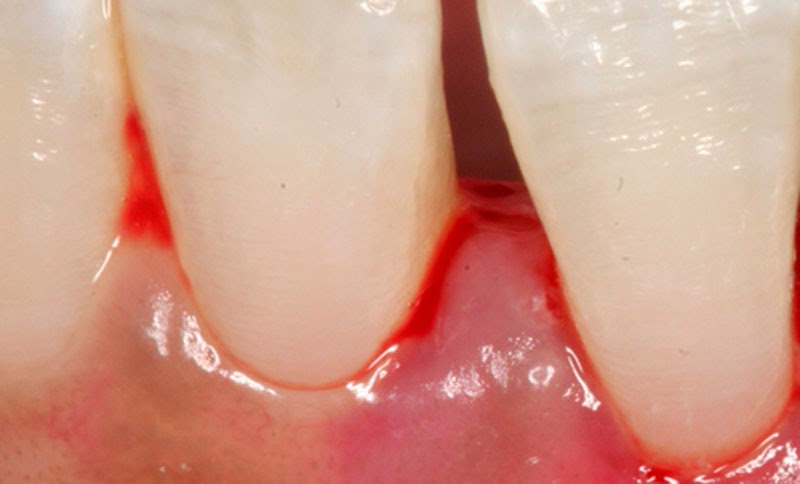

معلومات طبية